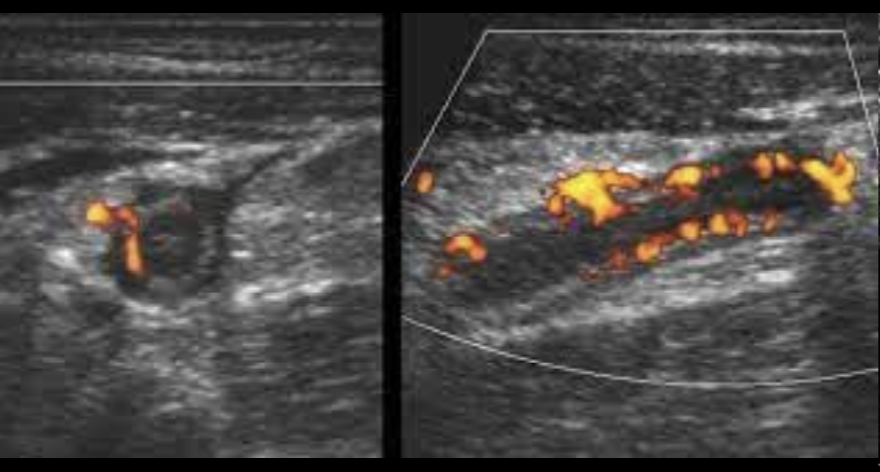

Ultil en niños

Apendicolito

Liquido libre

US en apendicitis

de lado US

De frente obstrucción luminal

Signo del anillo de fuego